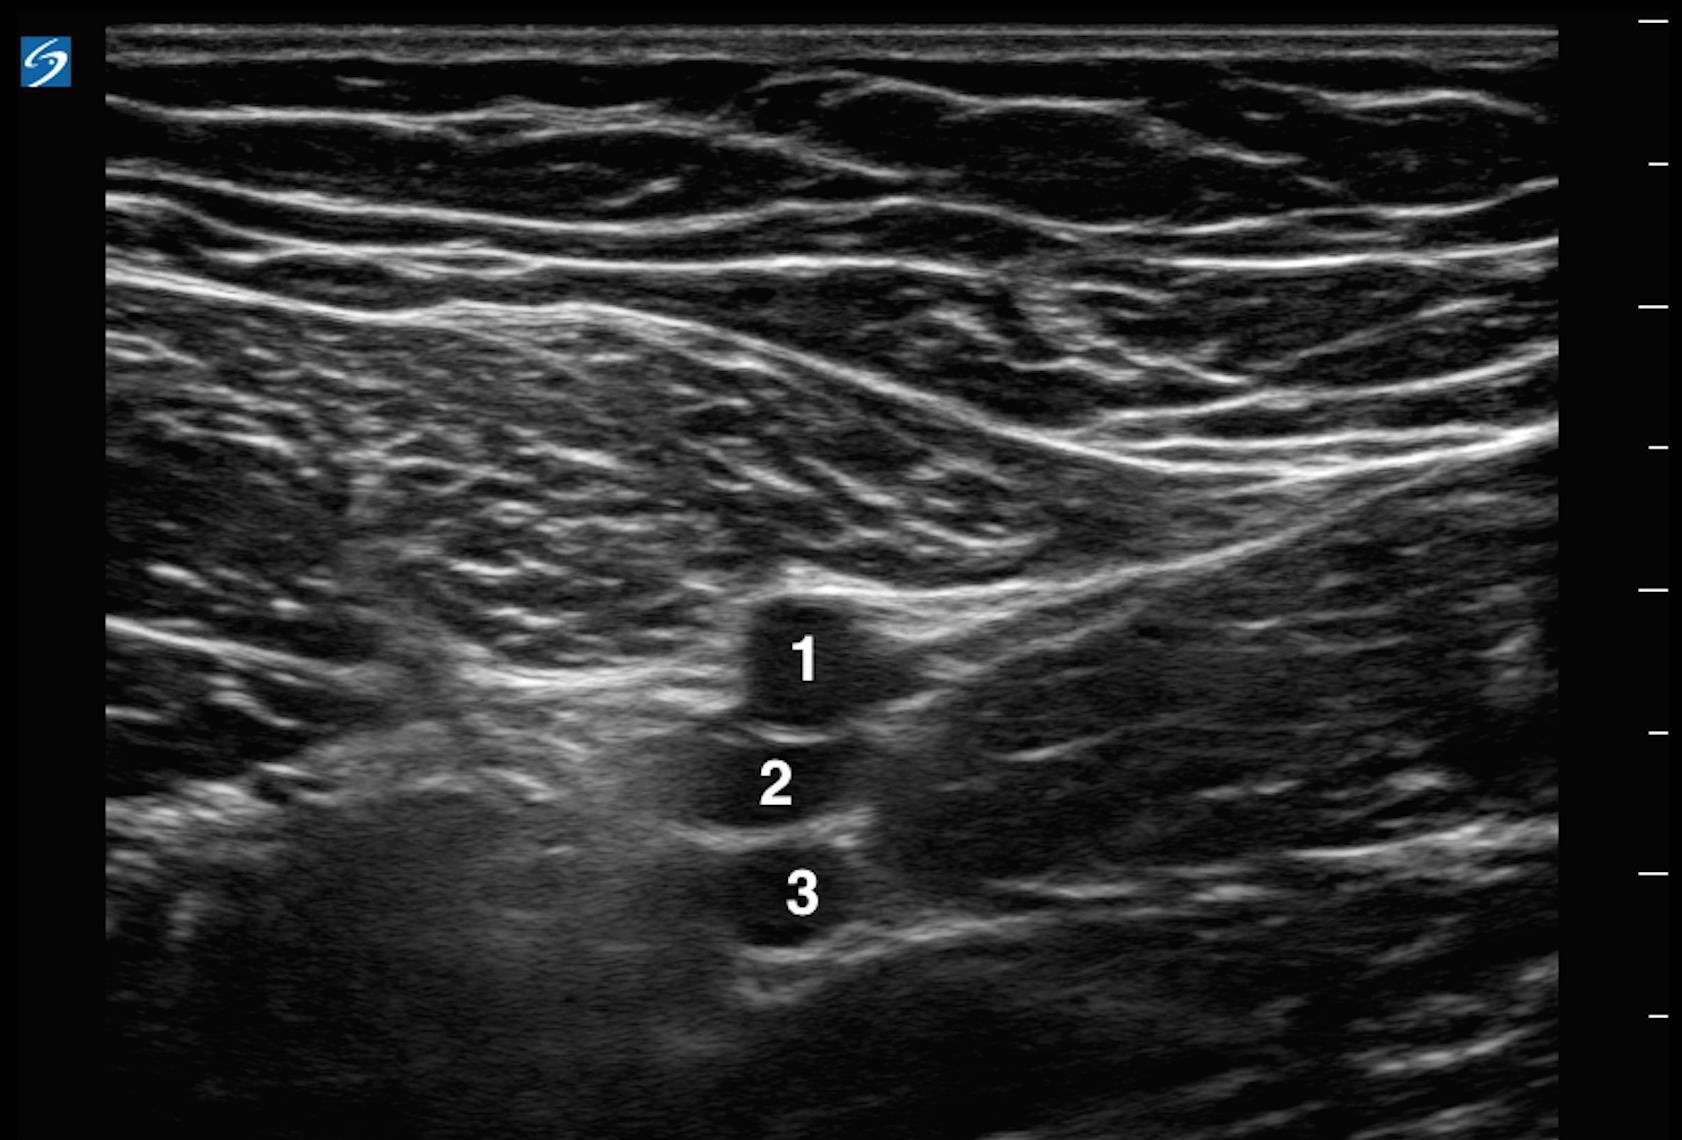

Tiefe Venenthrombose (TVT), Verzweigung der Vena femoralis communis (VFC) und der Vena profunda - Bild

1. Arteria femoralis communis (VFC)

2. Vena femoralis (VF)

3. Vena femoralis profunda